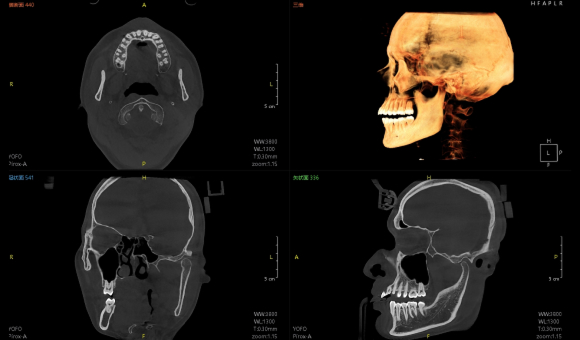

只需一次单圈扫描即可获得CT、3D全景和3D正/侧位影像,并能同时生成3D TMJ视图

提高诊疗效率,避免过度检查,减少患者所受的辐射

• CT

CT

24×21cm

非拼接超大视野